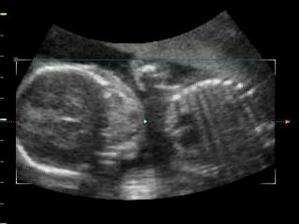

Tak jsme se dočkali!Dne 15.10.2007 nám bylo potvrzeno ultrazvukem těhotenství (5.týden)Na miminko se strašně moc těšíme a doufáme ,že vše bude probíhat tak jak má 🙂.Bereme vitamíny Gravital,osvědčily se nám i u Tomáška 🙂.Za 14 dní jdeme na ultrazvuk,tak se moc těším.Věciček máme hodně,ale samozřejmě budeme nakupovat o to víc pokud to bude holčička ,kterou bychom si mooooc přáli,ale hlavní je abychom byli zdraví 🙂.Dnes tj.28.11.jsem byla na 3D ultrazvuku (12.týden),tak jsem sem přidala nějake foto 🙂.Tak dnes 30.1.2008 jsem byla opět na 3D ultrazvuku (21.týden) a zjistili jsme ,že čekáme holčičku.Tak se nám povedl páreček.S manželem máme velkou radost,protože jsme si holčičku moc přáli 🙂).Tak ve 32.týdnu potvrzena holčička.Zatím vyhrává jméno Valérie.Ve 32.týdnu važíme cca 1924g 🙂).Tomíček se na sestřičku moooooc těší a už teď mi se vším pomáhá.